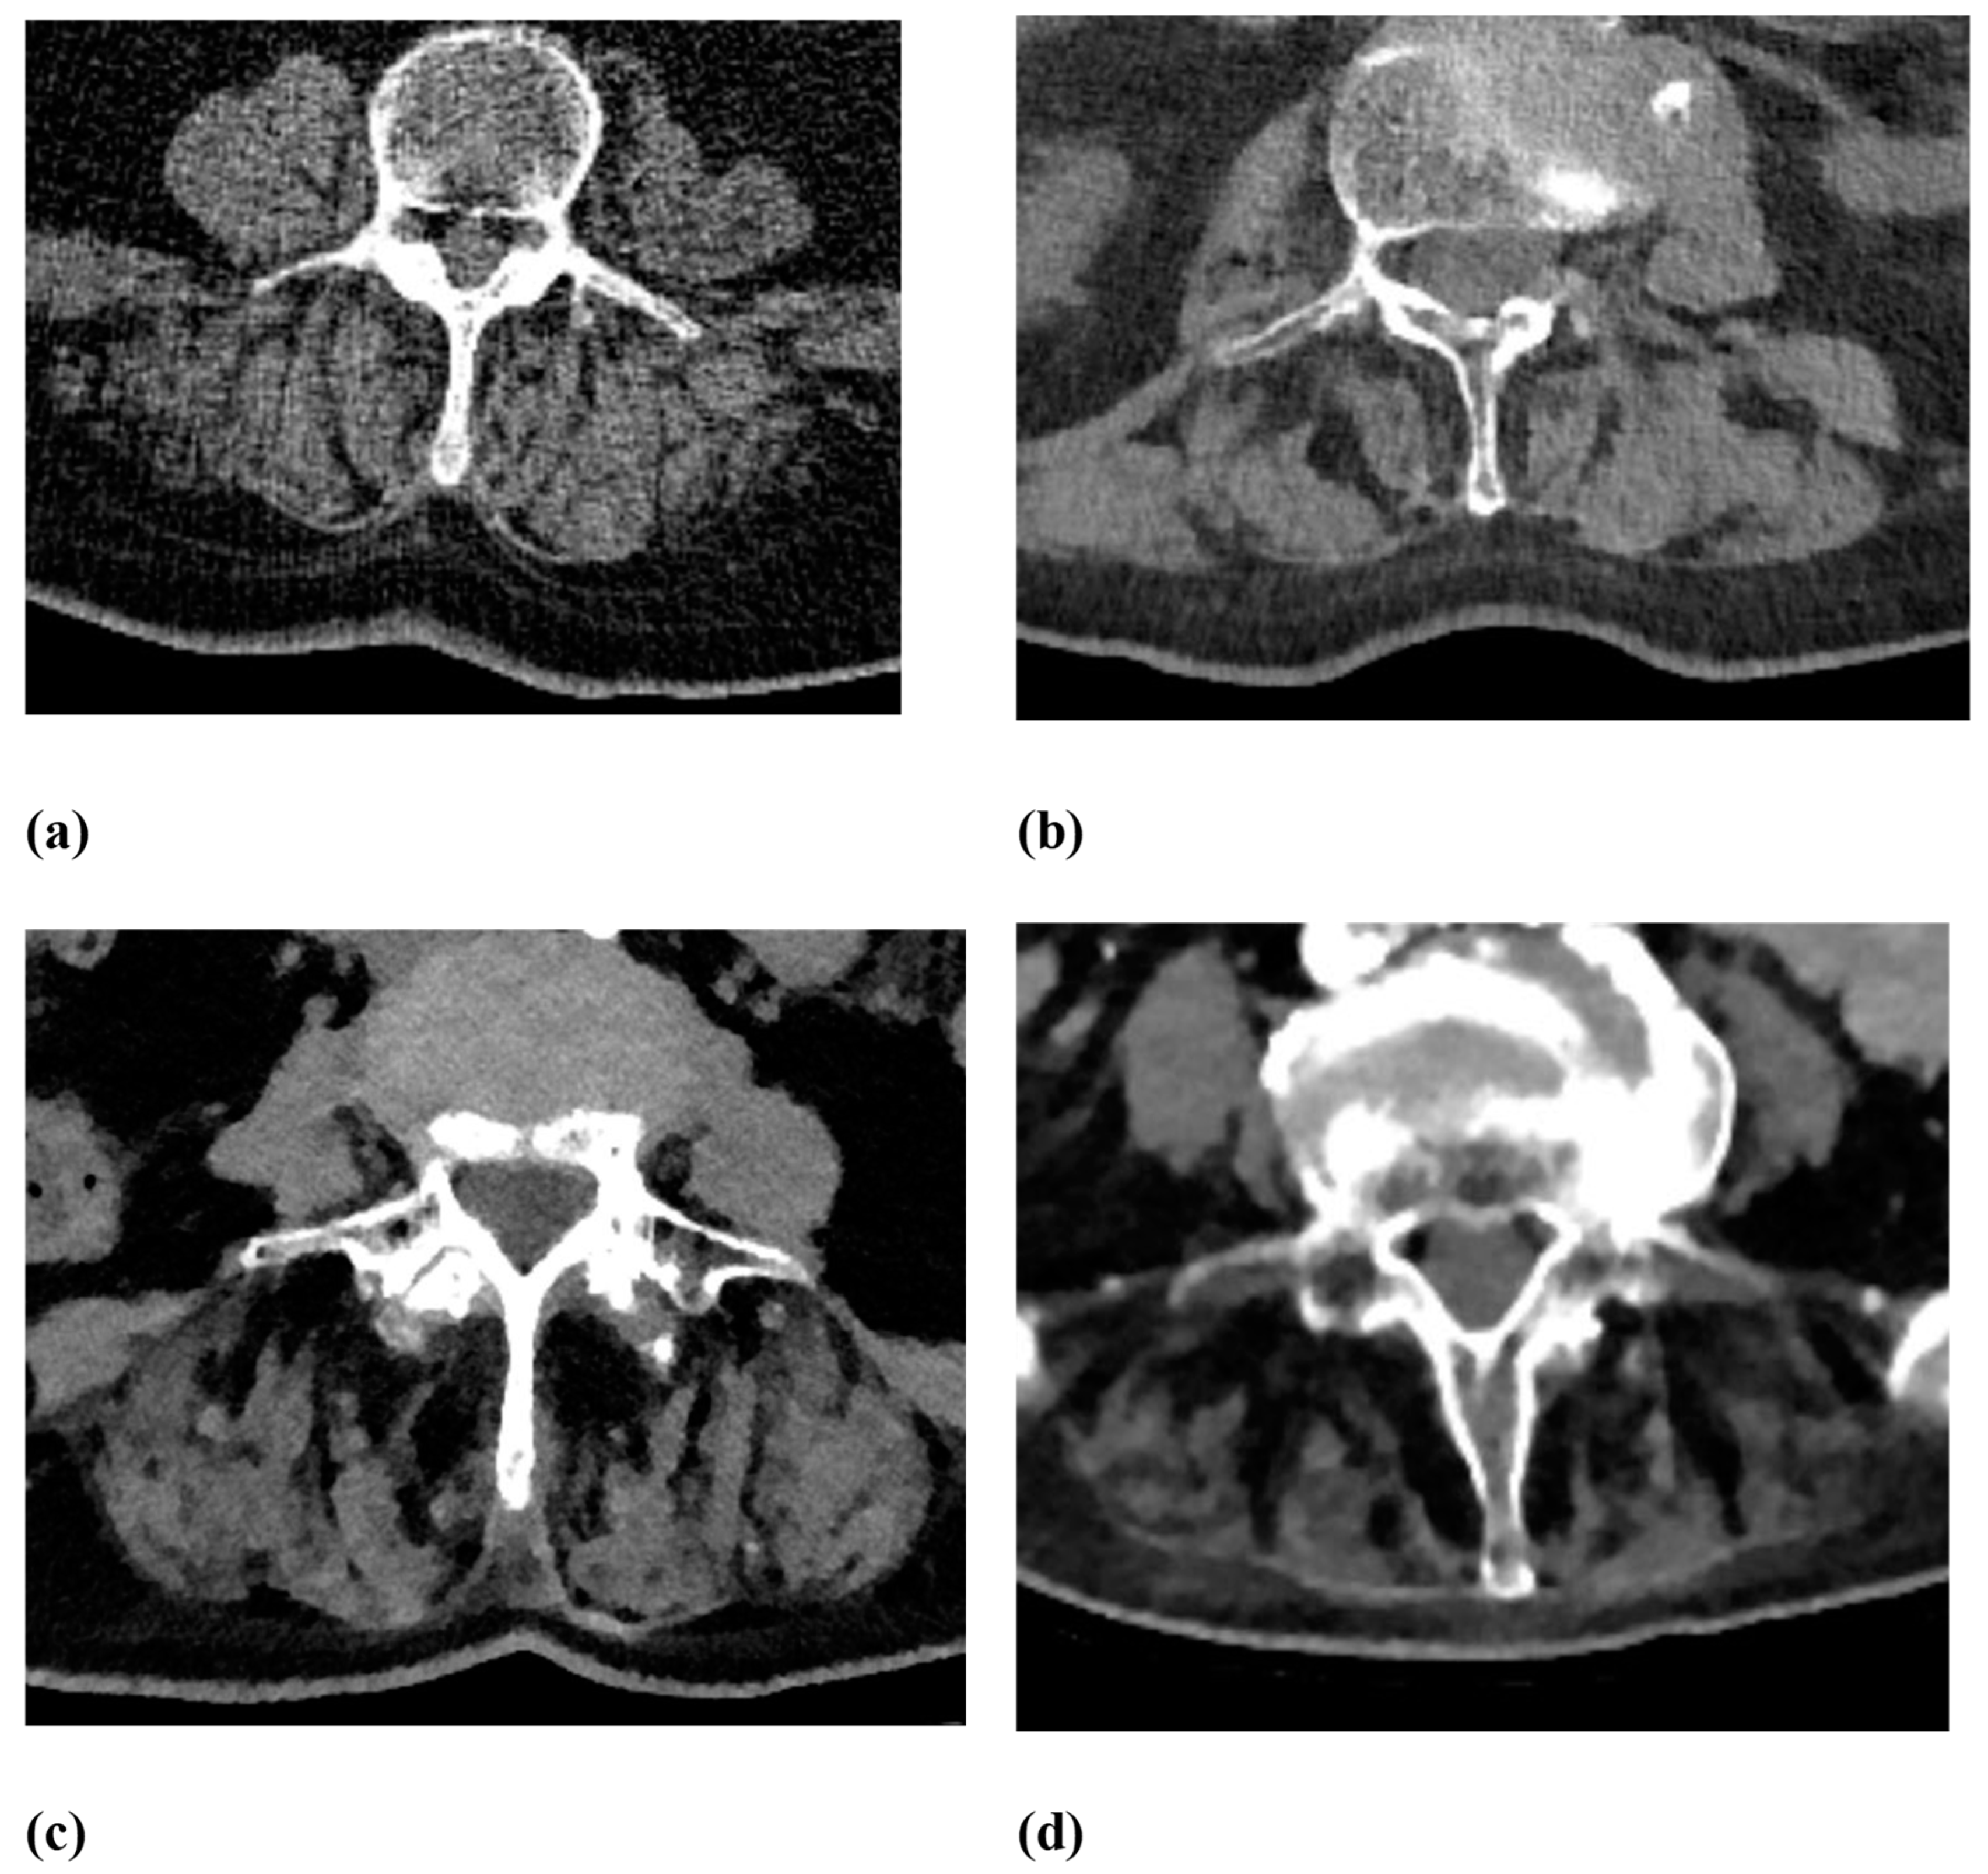

| Fatty degeneration of the autochthonous back muscles | Goutallier score 0–4:

|